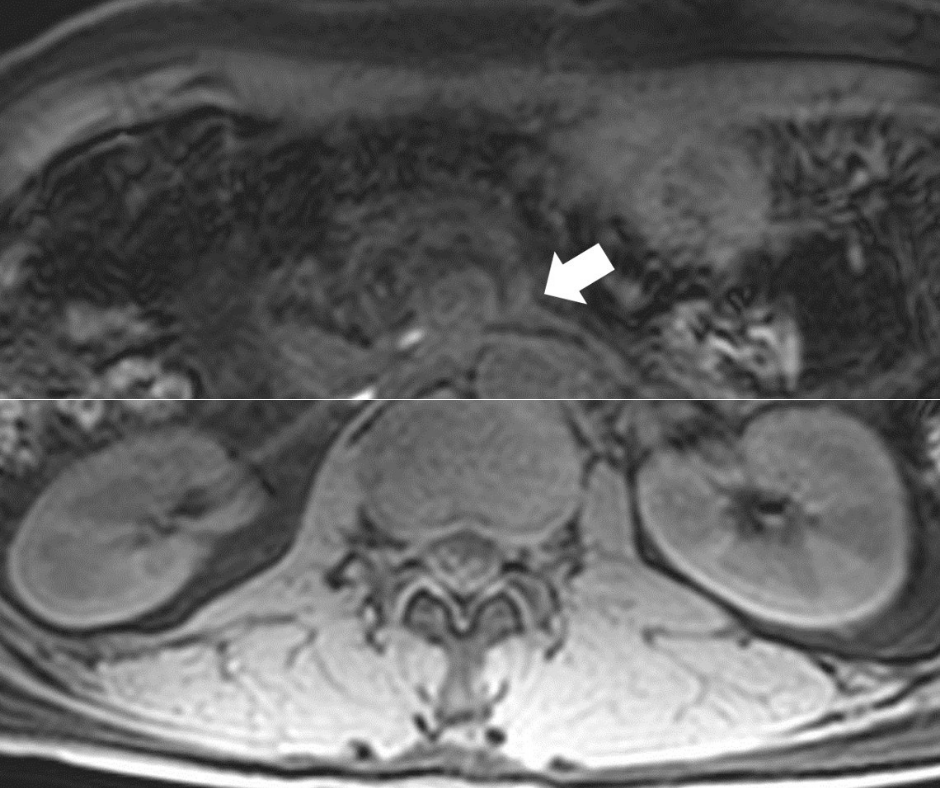

For post-op monitoring of patients who had pancreatic ductal adenocarcinoma (PDAC) resection, a new study showed that diffusion-weighted magnetic resonance imaging (MRI) had enhanced sensitivity for detecting recurrent tumors in comparison to conventional MRI.